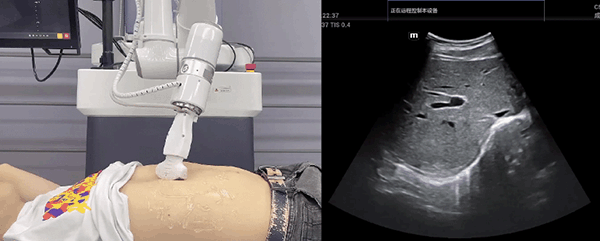

金年會(huì)jinnian(金字招牌)誠(chéng)信至上機(jī)器人末端搭載超聲探頭,可以對(duì)淺表小器官和外周血管、腹部(肝、膽、胰、腎等器官)進(jìn)行超聲檢查。